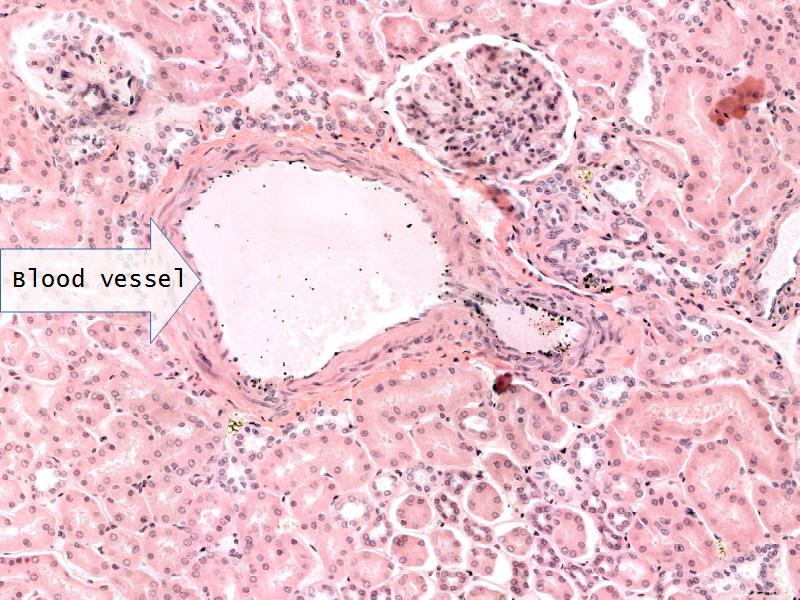

- Slide 76: Kidney